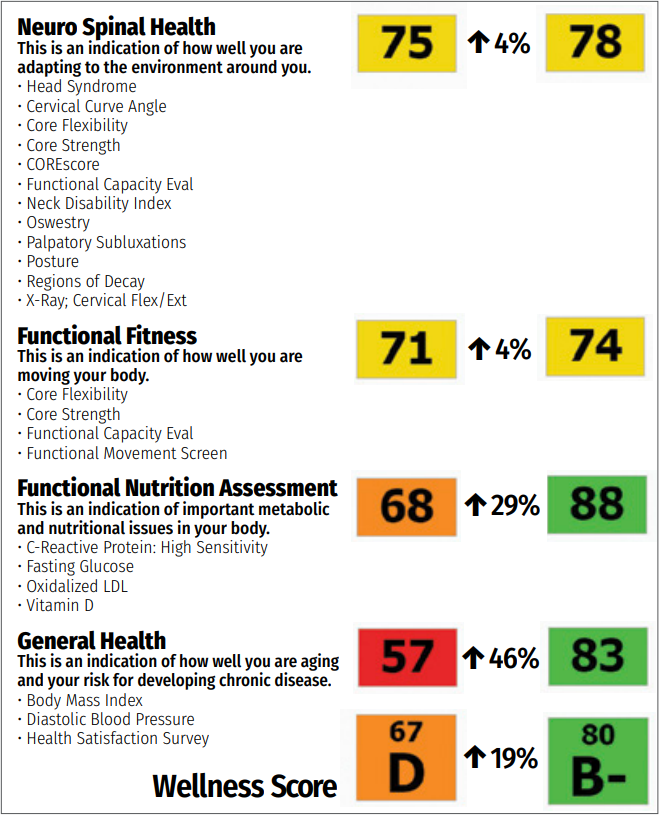

Once I have gathered that information, I create a Wellness Score (another application) to compile this data in an easy to understand format – a Report Card. After all, who doesn’t know what a report card means? And no one wants to have a bad grade. After they see their grade, the next question in their mind will be, “How can I improve?”

During re-exam time, I create another report that compares the data side-by-side to show the progress being made.

This does several things:

- Gives them the feedback that they need to show they are making progress.

- It helps them see that even if their symptoms may be gone, they still should remain under care to get an even better grade

- It gives them something to hang on the refrigerator for their family to see their progress. You will see that some patients will even post these reports to their social media.

- Keeps them motivated to keep their appointments and recommended treatment.

Now, I’m going to add in a little bit more of the Hawthorne Effect. I like to take these before and after reports and post them to our social media, telling the story of this patient and how proud I am of them (in a HIPAA compliant manner).

This shows potential patients the results that you get in your office, motivates current patients to keep up on their own progress, and if the patient is comfortable with it, they will share their report with their friends as well!

As an added bonus, you can send this data to the patients’ other practitioners to show the results you get in your office. Hopefully, they’ll refer more patients your way!